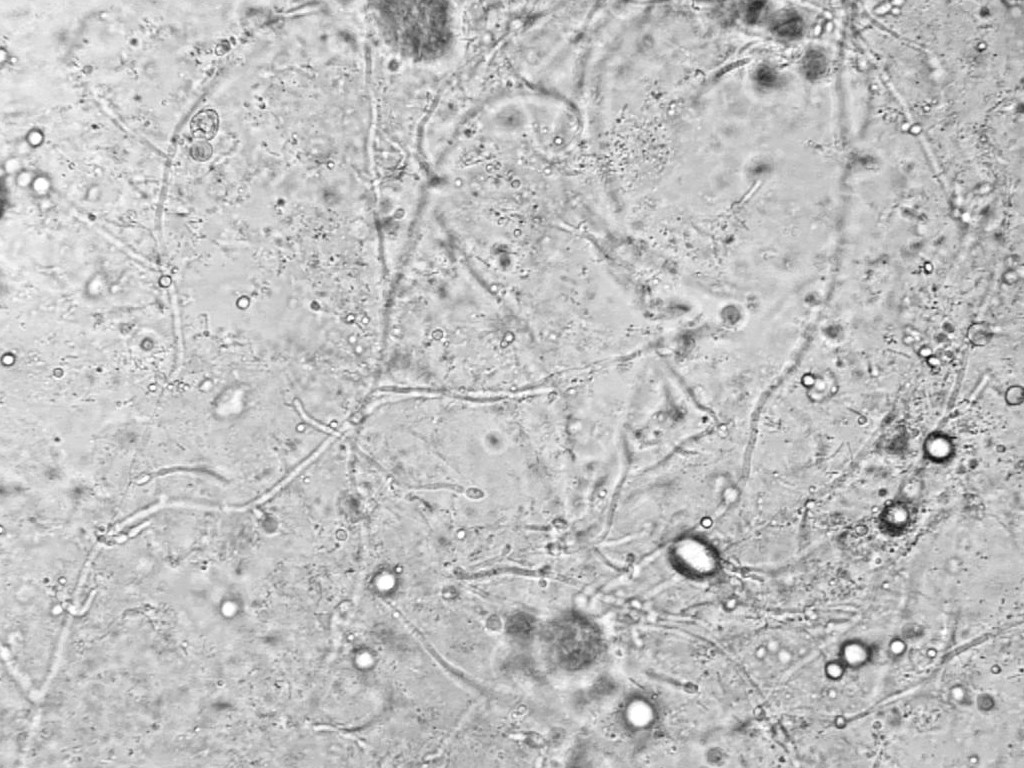

Diagnostiek:KOH preparaat van fluor, eventueel een kweek

op

Candida albicans. KOH: Breng wat fluor aan op een microscoopglas, afdekken

met dekglaasje en laat er een druppel 10% kaliumhydroxide (KOH) onder lopen.

Even verwarmen op / boven een warmte bron en dan beoordelen met de condensor

in een lage stand op hyphen, hyphen met knopvorming of gisten. Soms komt tijdens

het toevoegen van KOH een typische vieze geur vrij, een rotte vis geur (wordt

ook wel

amine test genoemd). Dit kan wijzen op een infectie met

Trichomonas

of

Gardnerella. In het KOH preparaat ziet men soms

clue cells, en soms ook nog

Trichomonas rondzwemmen, maar om die te zien is eigenlijk een natief preparaat

nodig, fluor gemengd met een druppeltje NaCl.

![Candia vaginitis (KOH) (click on photo to enlarge) [source: Mikael Häggström - Wikimedia - Creative Commons License 1.0 - Public Domain Image] Candia vaginitis (KOH)](../../../images/fluor-vaginalis-candida-1z.jpg) |

![Candia vaginitis (KOH) (click on photo to enlarge) [source: Mikael Häggström - Wikimedia - Creative Commons License 1.0 - Public Domain Image] Candia vaginitis (KOH)](../../../images/fluor-vaginalis-candida-2z.jpg) |

| Candia

vaginitis (KOH) |

Candia

Foto's: Mikael Häggström - Wikimedia (Creative Commons License

1.0

- Public Domain Image).